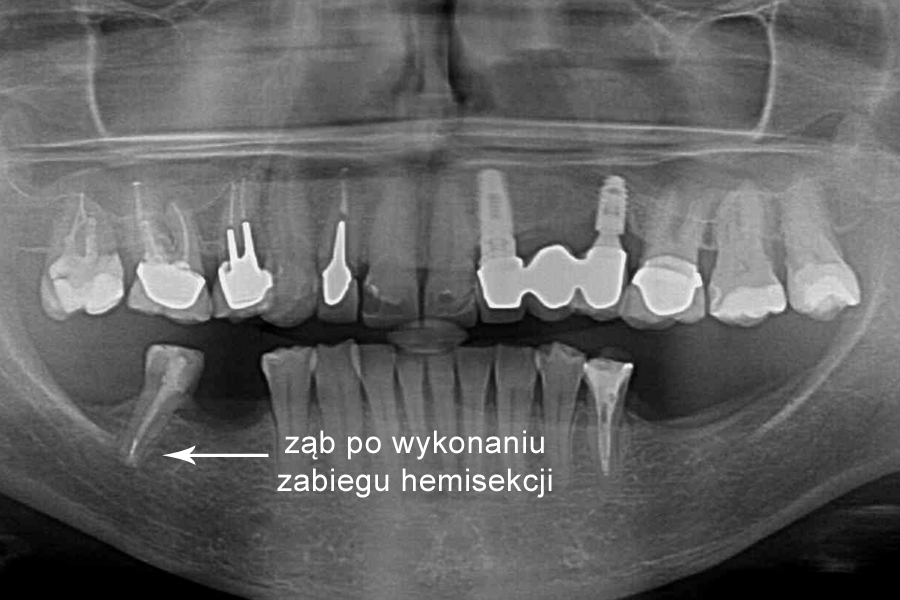

Hemisekcja – warto wiedzieć

Hemisekcja to zabieg polegający na separacji i usunięciu części korony i korzenia zęba dotkniętego nieodwracalnie procesem patologicznym. Pozwala to na zachowanie fragmentu zęba, który może być wykorzystany jako filar w trakcie dalszej rehabilitacji protetycznej. Pozostały fragment zęba może stanowić filar przy planowanej odbudowie protetycznej.